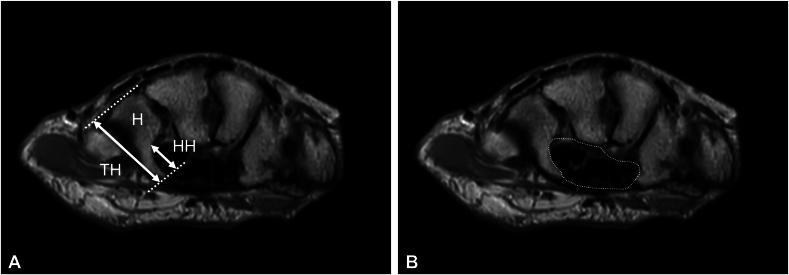

This retrospective study included 65 hands of 57 patients (8 men and 49 women; mean age, 64.9 years) who underwent endoscopic carpal tunnel release for carpal tunnel syndrome at our hospital between March 2016 and April 2022. The patients were diagnosed with carpal tunnel syndrome based on clinical observations and electrophysiological studies. On T2-weighted magnetic resonance axial images, the height of the hook of the hamate was measured from the bottom to the tip of the hook, and the total height of the hamate was measured from the dorsal surface of the hamate to the tip of the hook. A hook-to-height ratio of less than 0.34 was defined as hypoplastic, and its incidence was investigated. In addition, electrodiagnostic testing of sensory and motor nerve conduction of the median nerve and patient-reported outcome measurements, including Quick Disabilities of the Arm, Shoulder and Hand score, Boston carpal tunnel questionnaire, and visual analog scale score, were investigated at 6 months after surgery. Adverse events were collected from patient records.

这项回顾性研究纳入了2016年3月至2022年4月期间在我院因腕管综合征接受内镜下腕管松解术的57例患者(8例男性和49例女性;平均年龄64.9岁)的65只手。患者根据临床观察和电生理研究被诊断为腕管综合征。在T2加权磁共振轴向图像上,从钩骨钩的底部到钩尖测量钩骨钩的高度,从钩骨的背侧表面到钩尖测量钩骨的总高度。钩高比小于0.34被定义为发育不全,并对其发生率进行调查。此外,在术后6个月对正中神经的感觉和运动神经传导进行电诊断测试,并对患者报告的结局指标进行测量,包括手臂、肩部和手部快速残疾评分、波士顿腕管问卷和视觉模拟量表评分。从患者记录中收集不良事件。